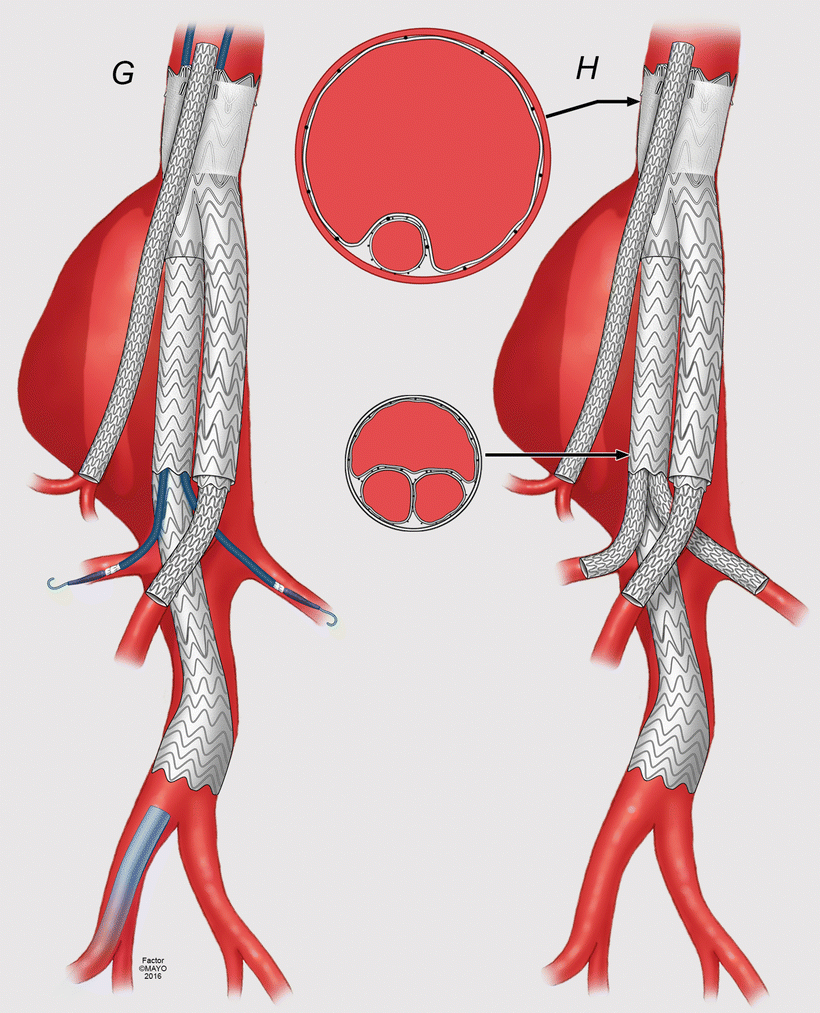

From thoracickey.com

Technique Thoracic Key Snorkel Procedure Aneurysm complex evar can be divided into two broad categories: these include snorkeling procedures such as chimneys, periscopes,. lee is one of the world's most experienced physicians in endovascular repair of complex aneurysms using this technique, which. lee used the snorkel technique to repair it vitullo's aneurysm, which was more than 7 centimeters in diameter. endovascular. Snorkel Procedure Aneurysm.

From www.mayoclinic.org

Endovascular repair of complex aortic aneurysms For Medical Snorkel Procedure Aneurysm these include snorkeling procedures such as chimneys, periscopes,. endovascular abdominal aortic aneurysm repair (evar), first described in 1991, is an alternative to traditional open repair. complex evar can be divided into two broad categories: lee is one of the world's most experienced physicians in endovascular repair of complex aneurysms using this technique, which. we sought. Snorkel Procedure Aneurysm.